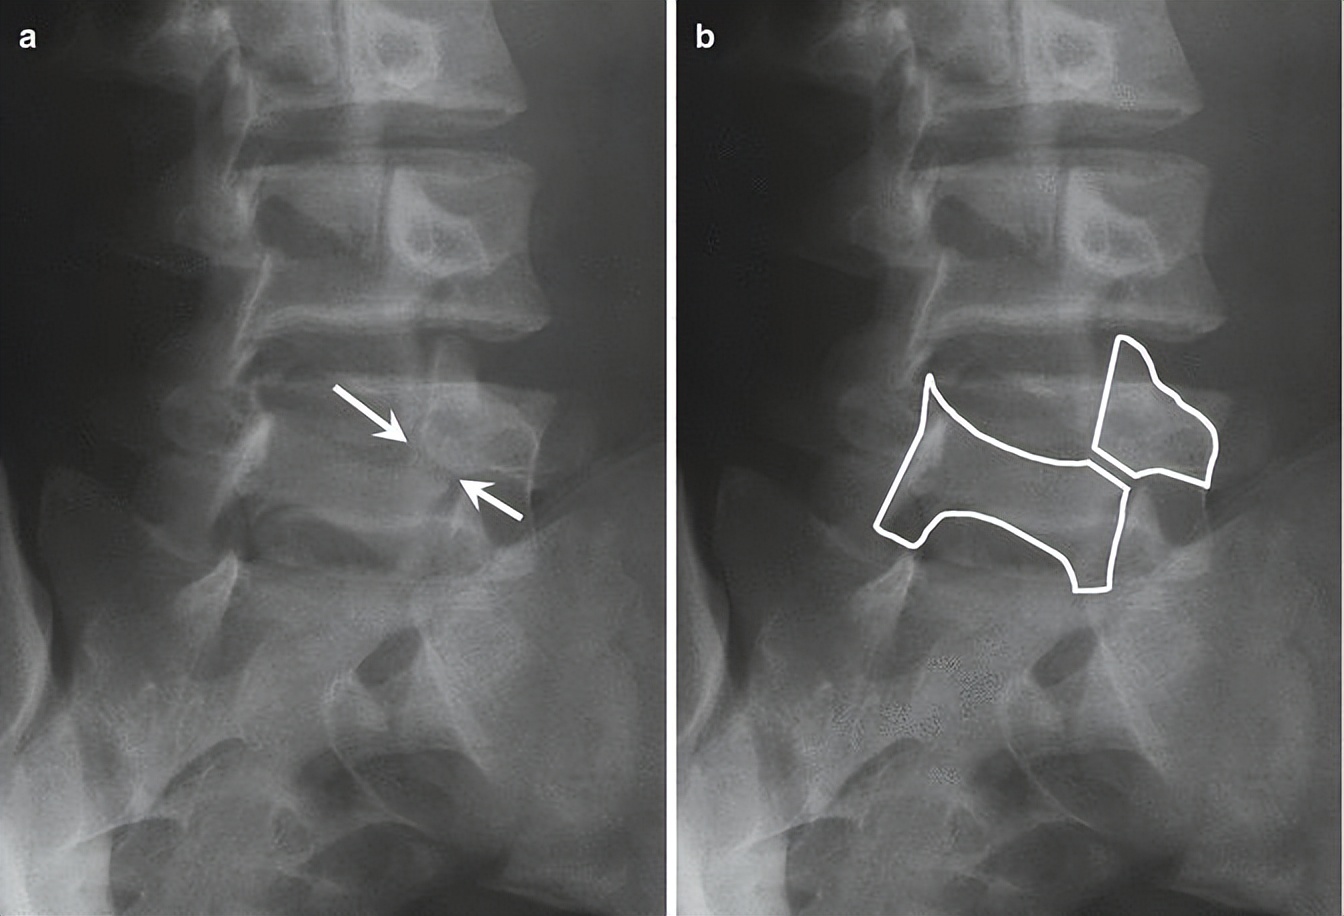

诊断腰椎峡部裂,腰椎双斜位片通常是需要的,表现为“苏格兰狗脖子”断了(见下图)。但对于一些隐匿的患者,腰椎双斜位片是看不出的,这时候需要行腰椎CT、MRI进一步明确诊断,少数部分需行核素骨扫描才能明确诊断。

1. 腰椎峡部和峡部裂在X线斜位片的表现

腰椎峡部在腰椎斜位片上常比喻为苏格兰狗(Scotty dog)的脖子

椎弓崩裂征象:X线腰椎45°斜位摄片示上关节突轮廓似"狗耳",横突似“狗头/嘴”,椎弓根似“狗眼”,下关节突似“狗前肢”,关节突肩部或称峡部似“狗颈部”。椎弓峡部崩裂时,“狗颈部”可见裂隙。

腰椎斜位片上的苏格兰狗和断裂的脖子(峡部裂)

再回顾下腰椎斜位视角的模式图,圆圈处为峡部